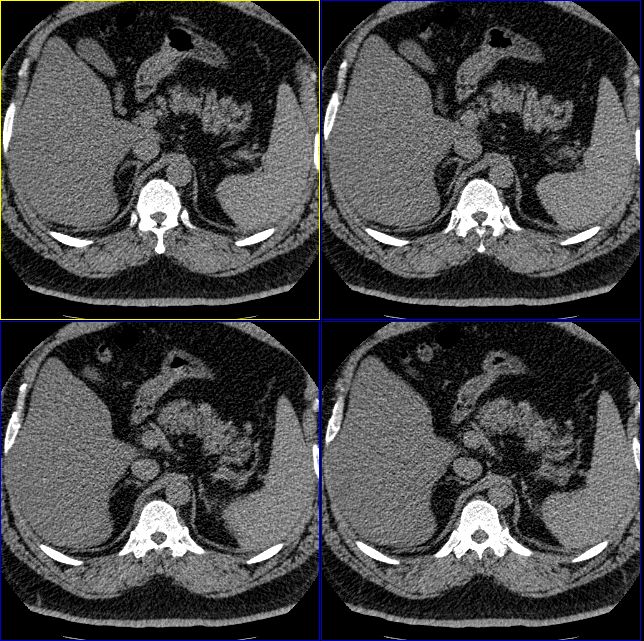

怎么回事啊,难道肾上腺没有问题么?右侧肾上腺有明显的脂肪性类圆形肿物,左侧也觉得有增生性改变。我们诊断为右肾上腺髓样脂肪瘤,左侧肾上腺增生。大家再仔细看看。

右侧肾上腺好像有一个类圆形的囊性包块,内部密度象是脂肪

1.肾上腺区囊性占位

2.脂肪肝